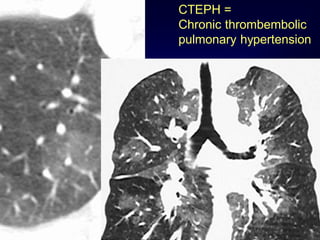

CTEPH =

Chronic thrombembolic

pulmonary hypertension

Mosaic Perfusion Chronic pulmonaryembolism LOOK FOR Pulmonary hypertension idiopathic, cardiac disease, pulmonary disease